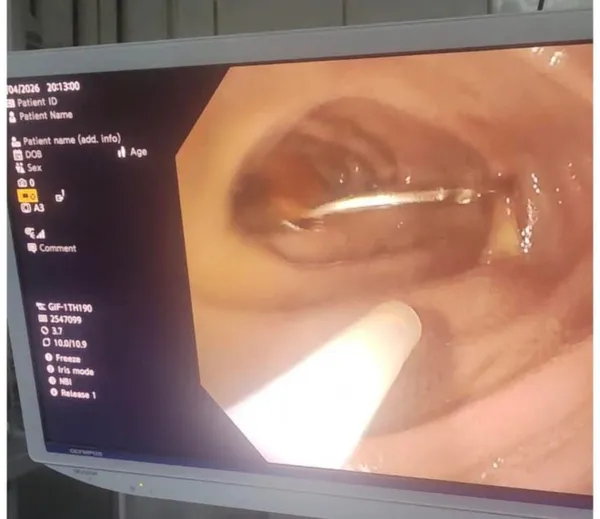

استقبل قسم الطوارئ بمركز كبد كفر الشيخ طفلًا صغيرًا بعد ابتعاله جسمًا حادًا (مسمار طويل) استقر داخل الاثنى عشر، مما تسبب في آلام شديدة بالبطن مع قيء متكرر، وكانت الحالة تستدعي تدخلاً عاجلاً، وتم تجهيز الطفل لاحتمال دخوله غرفة العمليات.

وتمكن فريق طبي بالمركز من التعامل مع الحالة بسرعة ودقة، وتم استخراج المسمار بنجاح كامل باستخدام المنظار دون الحاجة لأي تدخل جراحي، مما جنّب الطفل مخاطر الجراحة وسمح له بالخروج بحالة مستقرة وآمنة.

وتكون الفريق الطبي من الدكتور محمد حمدين عجلان، استشاري الجهاز الهضمي والكبد والمناظي، والدكتور محمود حسين، والدكتور عبد الرحمن الصفتاوي، والدكتور علي النواصرة من قسم التخدير، وذلك تحت رعاية الدكتور ياسين رمضان، مدير عام مركز كبد كفر الشيخ.